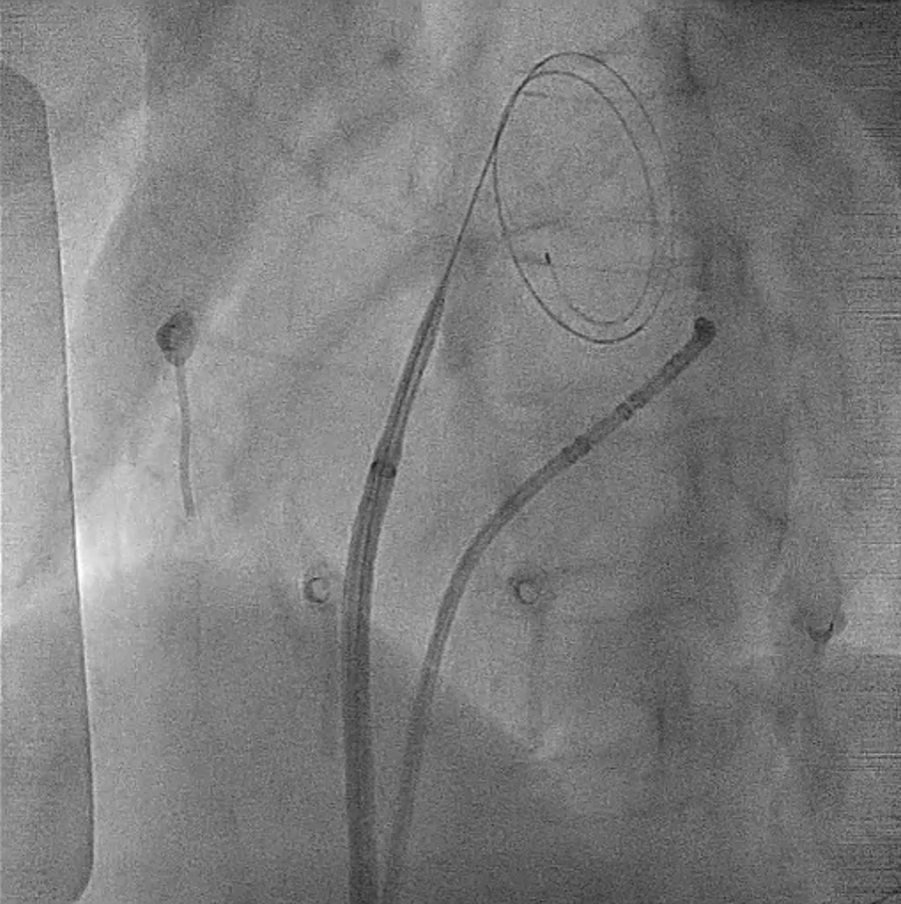

Under fluoroscopic guidance, the interatrial septum was identified, and the tip of the guidewire was positioned against the septum. TSP was then successfully performed using the electrocautery technique similar as above (Figure 3; Supplementary Video S2), allowing the smooth introduction of the SL0 sheath and its dilator into the LA. A second puncture with Agilis NxT Steerable Introducer (Abbott Medical Australia Pty Ltd) was performed using the same technique. The catheter ablation was subsequently completed without complications.

Figure 3

Transseptal process under fluoroscopy. The GMS-1 guidewire became pigtail configuration after crossing the septum. For a complete video clip, please refer to Supplementary Video S2.